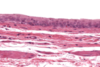

Esophagus - musculares externa, submucosa, mucosa

Esophagus – mucosa, submucosa, muscularis externa

Esophagus – mucosa – stratified squamous non-keratinized ep, lamina propria with small blood vessels, muscularis mucosa (smooth muscle)

Esophagus - submucosa (DICT) with blood vessels